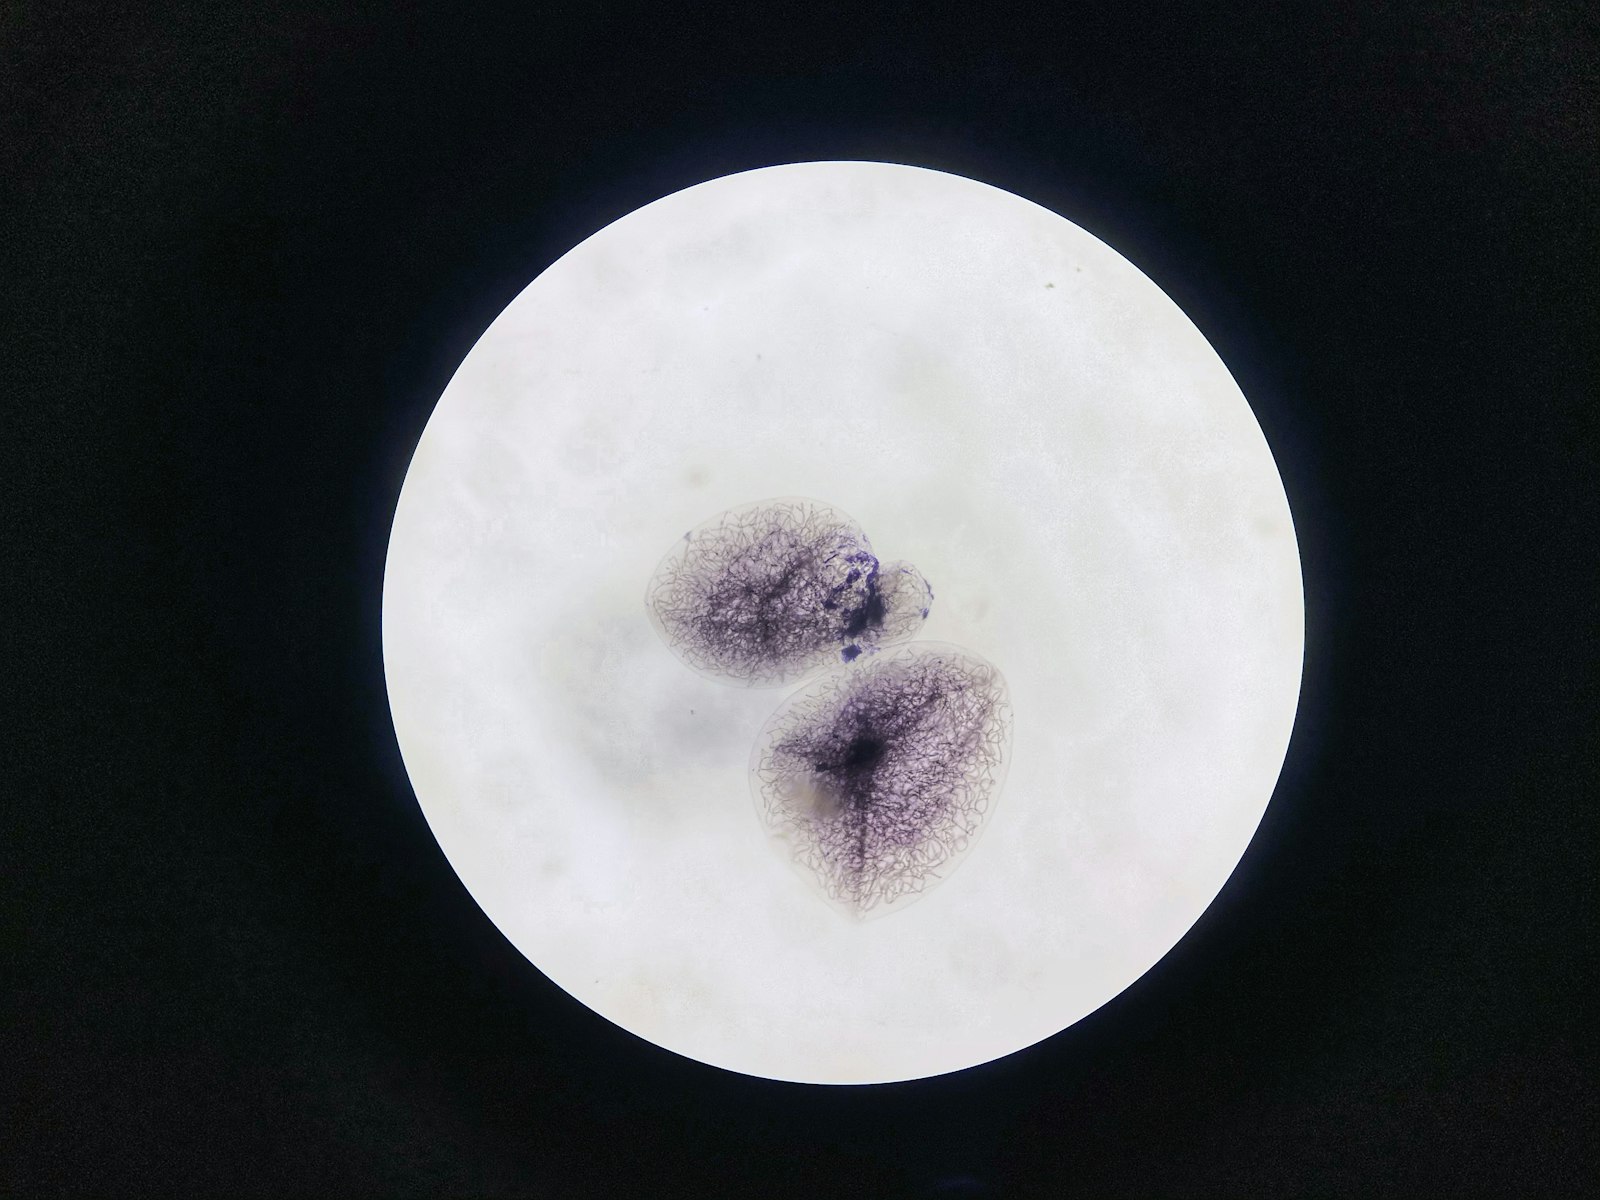

Embryology scientist reviewing microscope images in a clinical lab

• Developmental competence: Beyond chromosomes, laboratory observations track how embryos progress, including energy use and spindle integrity. These age-related shifts are documented in embryology labs, not something your period can diagnose.

Embryologist examining a fertilized egg under magnification in an IVF lab dish